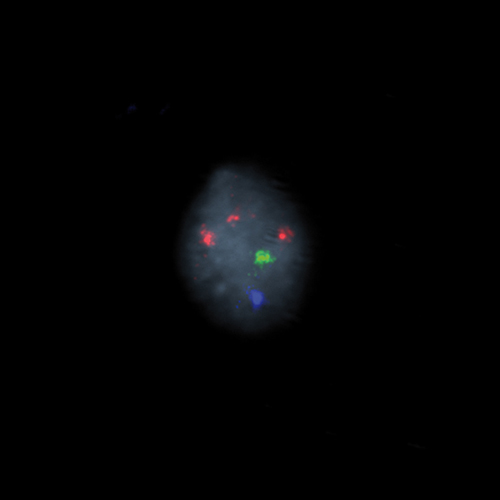

Hybridization of the RCAN1 (21q22), SE X, SE Y probe to a male metaphase spread showing normal pattern (2R1G1B)

Chromosomal abnormalities involving the X and Y chromosome (sex chromosomes) are slightly less common than autosomal abnormalities and are usually much less severe in their effects. The high frequency of people with sex chromosome aberrations is partly due to the fact that they are rarely lethal conditions. - Turner syndrome occurs when females inherit only one X chromosome - their genotype is X0. - Metafemales or triple-X females, inherit three X chromosomes - their genotype is XXX or more rarely XXXX or XXXXX. - Klinefelter syndrome males inherit one or more extra X chromosomes - their genotype is XXY or more rarely XXXY, XXXXY, or XY/XXY mosaic.

RCAN1 (21q22), SE X, SE Y